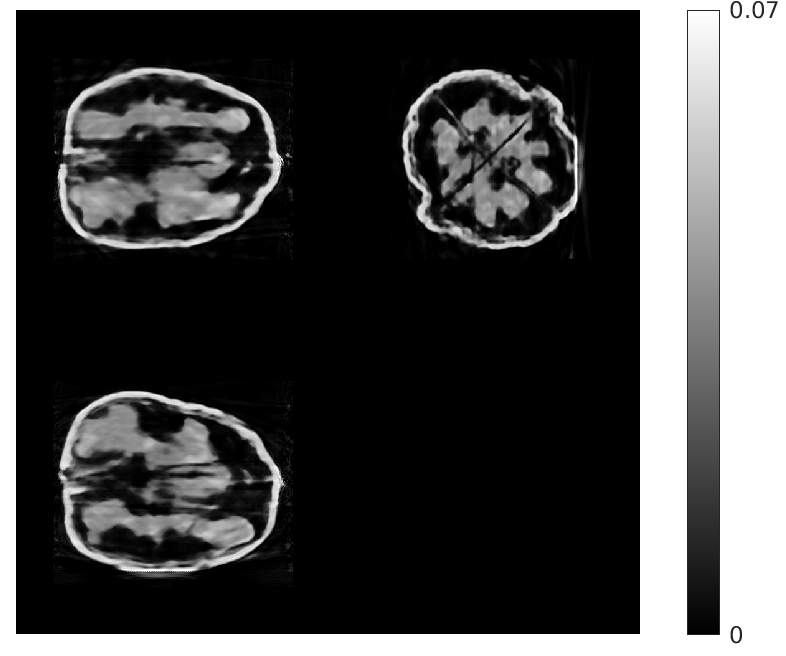

Fig. 5 shows walnut 1 from our test dataset being progressively reconstructed from 8 projections across the stages of our algorithm; as the stages progress, more features are restored in the reconstructed walnut, until the improvements become incremental. The residual streaking artifacts outside the walnut are mitigated in the reconstructions from the third and fourth stages.

| Stage 1 | Stage 2 |

![]() |

| (a) (MAE: 0.32) | (b) (MAE: 0.29) |

| Stage 3 | Stage 4 |

| (c) (MAE: 0.27) | (d) (MAE: 0.26) |